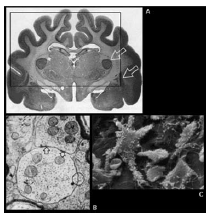

La unidad estructural y funcional del sistema nervioso queda fundamentalmente constituida por las neuronas y las células gliales. Se calcula que existe alrededor de 100 billones de neuronas en el sistema nervioso humano, y unas 10 veces más de células gliales. En cada una de las células, podemos distinguir diferentes componentes u orgánulos, y dentro de éstos, podemos llevar a cabo un análisis molecular y estudiar canales, receptores, e incluso el ADN neuronal. Por tanto, en un extremo tendríamos el nivel celular y molecular, y en el otro extremo de la escala tendríamos la anatomía en el nivel macroscópico, donde es posible establecer diferentes divisiones sin necesidad de recurrir a los aumentos del microscopio.

Figura 1. Diferentes niveles de estudio del cerebro humano. Cuando se analiza la anatomía cerebral, se puede abordar su estudio desde un punto de vista macroscópico o bien a través de los diferentes componentes que lo integran: las células nerviosas, partes de éstas, las sinapsis, la estructura interna de la célula, las moléculas presentes en la membrana o en el citoplasma o incluso los genes que se expresan en el tejido nervioso. (Adaptada de Rosenzweig y col., 2001).

Partiendo de la organización de nuestro sistema nervioso en diferentes niveles de complejidad estructural, es necesario atender en primer lugar a los principales elementos celulares, fisiológicos y moleculares como punto de partida para poder comprender otros niveles de organización más global, como la conformación del cerebro por núcleos, capas y vías de proyección, la estructuración de los diferentes sistemas neurales y la descripción macroscópica cerebral.